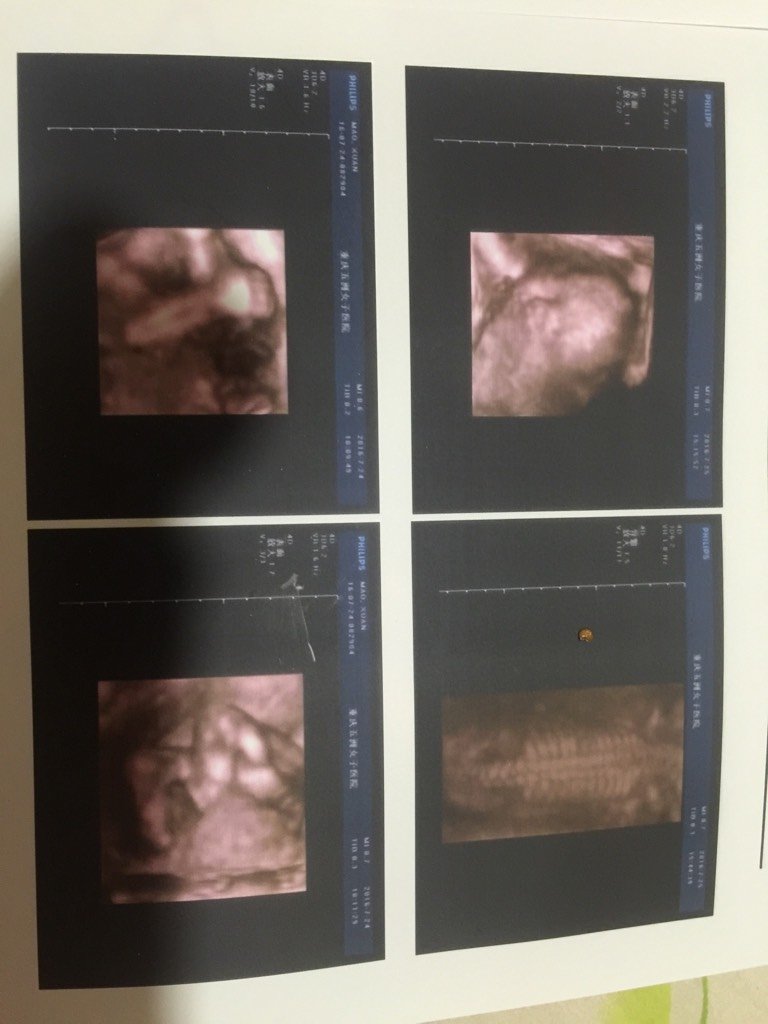

今天才做的四维,我和老公觉得不管是弟弟还是妹妹都无所谓,但是又很好奇到底是妹妹还是弟弟,有没有谁会 今天才做的四维,我和老公觉得不管是弟弟还是妹妹都无所谓,但是又很好奇到底是妹妹还是弟弟,有没有谁会看呀 点击展开 安大美丽 2016-07-25 23:04 为您推荐: 其他回答 男宝宝!! o(^_^)o、 2016-07-25 23:43 不会。看这个看不出来的 150*****923_zV9O 2016-07-25 23:17 不会看,祝宝宝身体健康 か此女子不特别★却是唯一 2016-07-25 23:15 看不出来, 嗼ら悲傷 2016-07-25 23:15 问医院!!! 每天好 2016-07-25 23:14 加载更多 相关问题 四维通过,还是有点好奇,是弟弟还是妹妹 不知不觉已经34周了,越来越好奇你的性别了,宝妈们帮忙看看是弟弟还是妹妹 时间快点过、期待着我宝宝到来,是妹妹还是弟弟呢?嘻嘻、啥都爱、就是好奇心而已